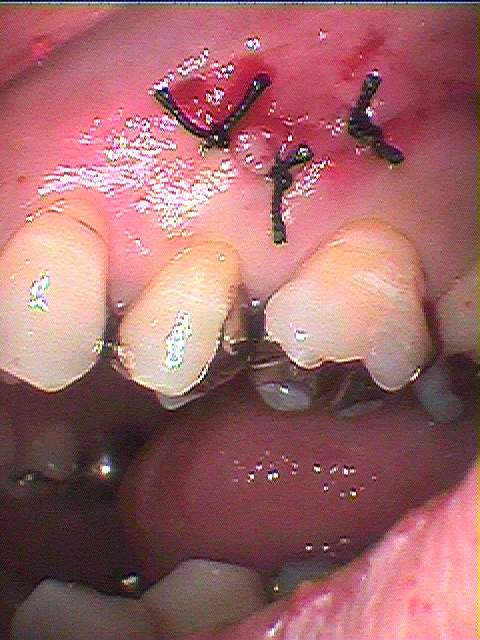

縫合して終了となります

しっつかりと骨補填材を詰め込んでいるのがデンタルレントゲンにてわかると思います